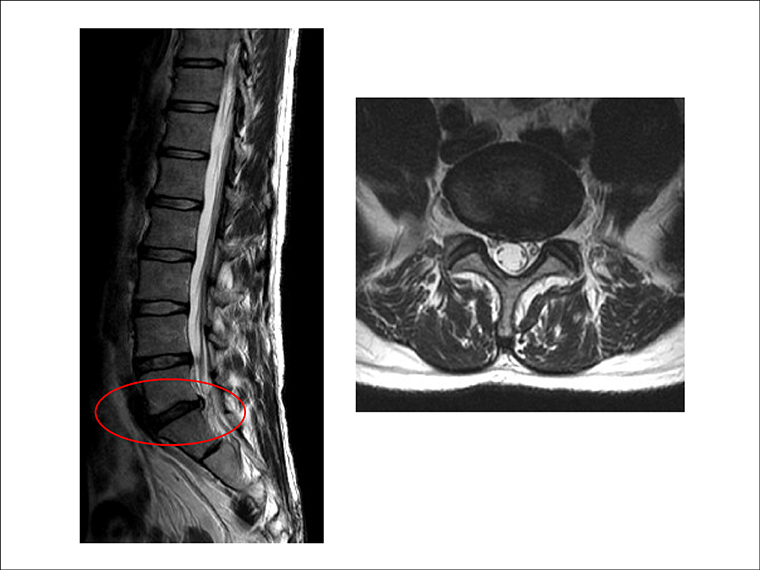

Q. 椎間板性腰痛とはどのようなものですか?

A. 椎間板は体を支える大事な部分で、常に負担がかかっています。20代頃から少しずつ傷み始め、蓄積されたダメージが限界を超えると亀裂が入り、痛みとして現れます。

腰痛には様々な原因がありますが、その一つが椎間板性腰痛です。